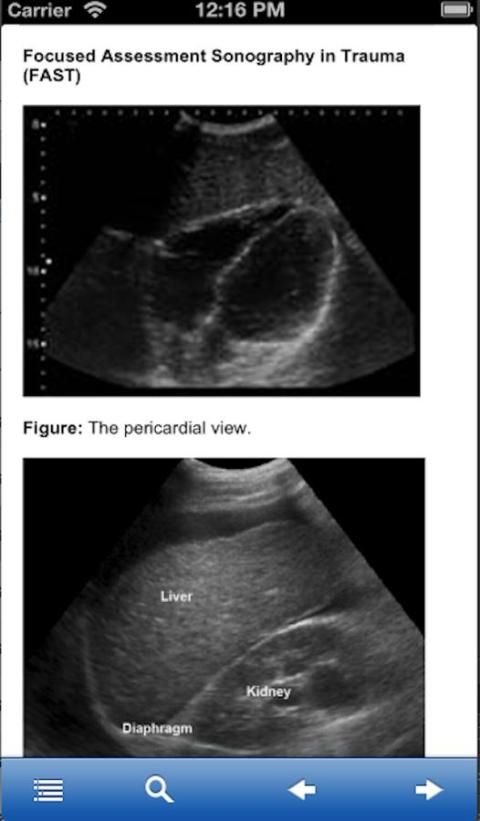

आकलन सोनोग्राफी ट्रामा केंद्रित